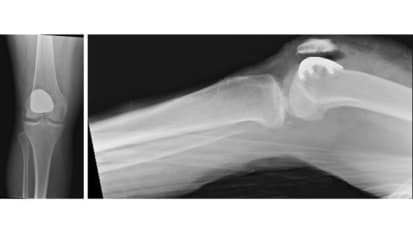

Innovating Treatment for Recurrent Patellar Instability

Andrew Cosgarea is contributing to a better understanding of patellar instability. Unlike other knee injuries that he treats — such as ACL tears, which tend to be similar in pathology — patellar instability cases “have a tremendous amount ...

Surgeon Expands Patellofemoral Research, Women’s Sports Medicine